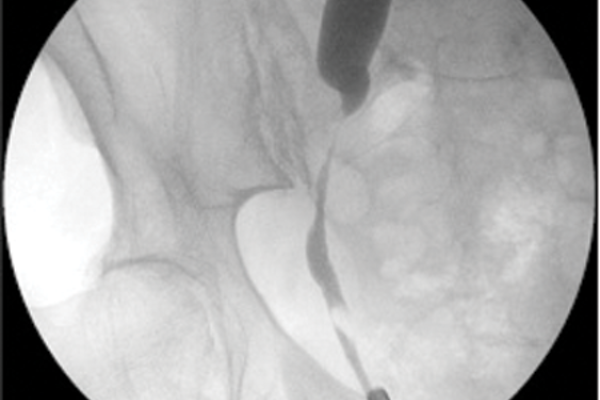

Urethral pathology